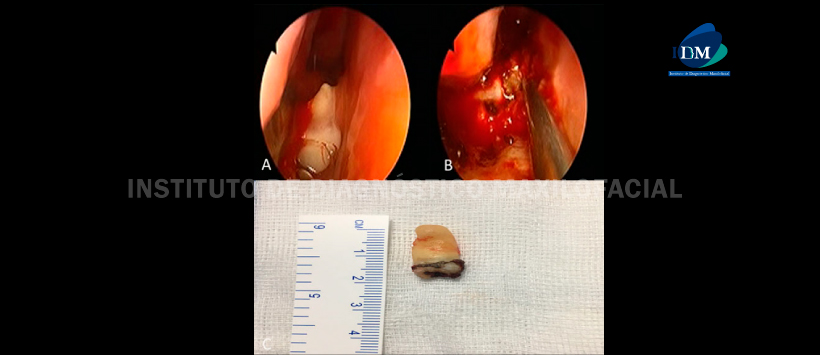

La extracción de el diente ectópico con ayuda de endoscopia presenta algunos ventajas como buena iluminación, visualización clara y disección precisa. Además, esta técnica permite una reducción de la morbilidad postoperatoria y un período de hospitalización más corto.

El paciente se sometió a una endoscopia transnasal del orificio nasal derecho para extraer el diente supernumerario debajo anestesia general. El diente estaba recubierto por mucosa nasal pero era parcialmente visible en el piso nasal. (Figura 2)